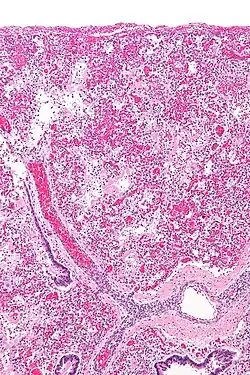

Leukocyte-mediated pulmonary inflammation is a key pathophysiological mechanism involved in ARDS.[2] This is presumed to cause Diffuse Alveolar Damage (DAD) [Fig 2]. On histologic examination, DAD is present in 40-60% of patients clinically diagnosed as having ARDS.[3]